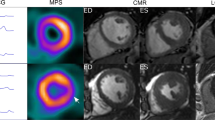

Several non-invasive myocardial imaging methods, such as three-dimensional (3D) speckle-tracking echocardiography (STE) and cardiac magnetic resonance (CMR), have been used to assess LV mechanical contraction patterns and investigate the influence of the associated electromechanical characteristics to the CRT response.8,9,10,11,12 Sohal et al. demonstrated a strong relationship between LV electrical activation sequences and mechanical contraction pattern, and reported that the U-shaped LV mechanical contraction pattern identified by CMR had an increased response rate to CRT as well.10 However, the limited availability, long examining and imaging time, and inability to scan patients with implanted devices impede the development of CMR in routine assessment of contraction patterns.13

The contraction patterns were assessed by 2 independent observers. Two types of LV mechanical contraction patterns were demonstrated in our study (Figure 2). The U-shaped contraction pattern (Figure 2A) was defined as the presence of a significant delay caused by a block line in the direction of LV contraction propagation. The non-U-shaped pattern was defined as homogenous (Figure 2B) or other heterogeneous (Figure 2C) contraction pattern.

Examples of different contraction patterns. (A) The regional contraction onsets (left) and contraction sequence (right) of an example with the U-shaped mechanical contraction pattern. The anteroseptum (blue) contracted firstly, and then the contraction propagated from the apex to the lateral wall, but it was blocked at the anterior wall, showed by yellow arrows. The anterior wall became the latest contraction site (red). (B) The regional contraction onsets (left) and contraction sequence (right) of an example with the non-U-shaped contraction pattern (homogeneous pattern). There was no apparent contraction delay in the propagation direction from the septum to lateral wall. (C) The regional contraction onsets (left) and contraction sequence (right) of an example with the other type of the non-U-shaped contraction pattern. Multiple sites with the significant contraction delays were present in this patient